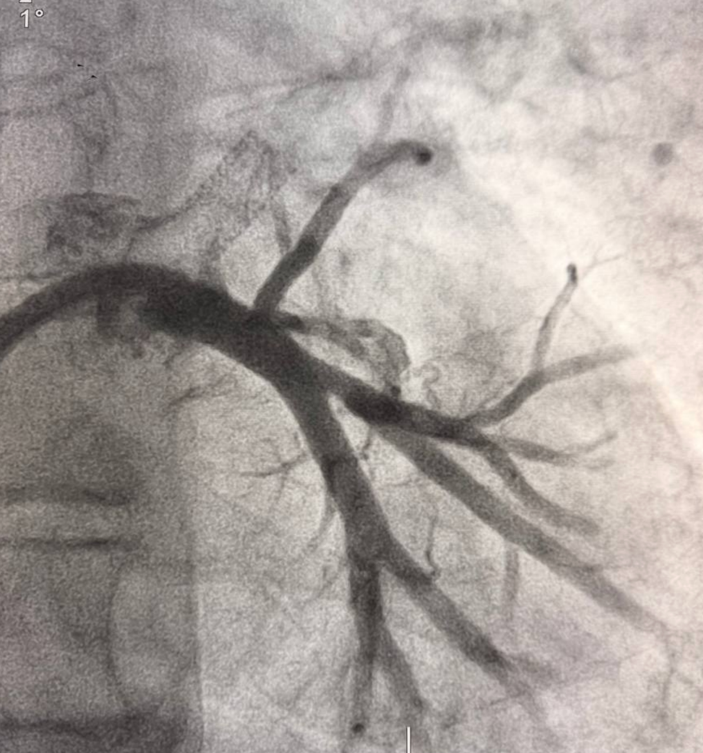

Вмешательство проводилось через бедренный венозный доступ под местной анестезией. Основная сложность операции заключалась в полной окклюзии обеих легочных вен и необходимости точной навигации инструментов в условиях ограниченной визуализации. После реканализации поражённых участков были имплантированы стенты, обеспечившие надёжное восстановление просвета сосудов и полноценный венозный отток из лёгких.

В результате кровоток по левой верхней и левой нижней легочным венам полностью восстановлен. Состояние пациента стабилизировалось, одышка регрессировала. В настоящее время пациент чувствует себя хорошо.